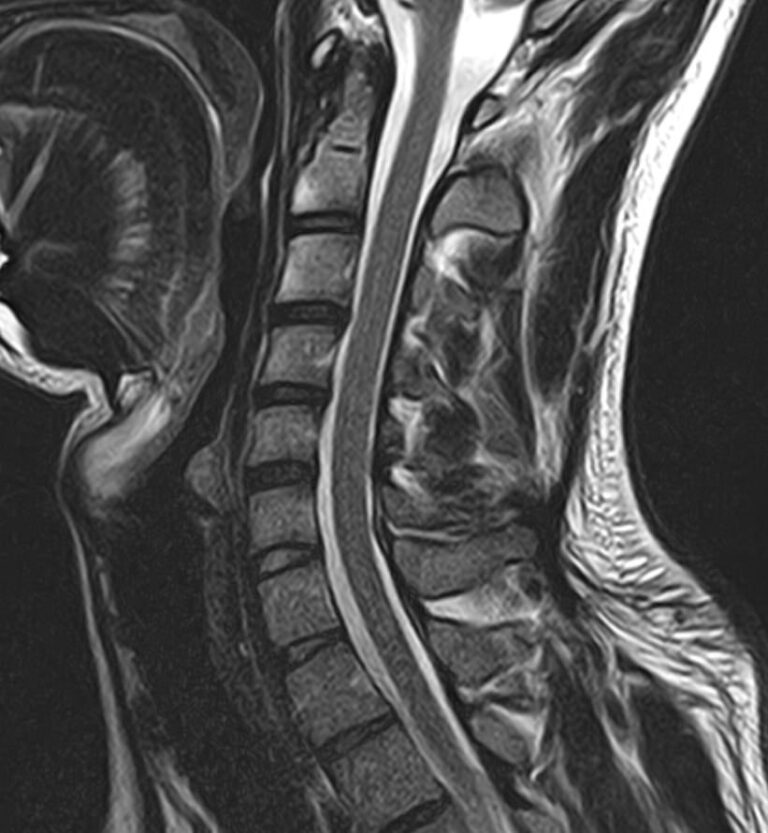

В клинике «Доступная медицина» можно пройти комплексное обследование, включающее в себя два протокола сканирования близко расположенных друг от друга анатомических областей – шейного отдела позвоночника и головного мозга. Метод комплексного обследования оценивает состояние всех структур головного мозга и самого верхнего сегмента позвоночного столба, который включает в себя 7 шейных позвонков, спинной мозг с отходящими от него нервными корешками и окружающими мягкими тканями.

Сканирование проводится на современном высокопольном магнитно-резонансном томографе закрытого типа TOSHIBA VANTAGE TITAN 1,5 Тесла. Магнитно-резонансный томограф производит послойное сканирование исследуемой зоны в разных плоскостях, затем при помощи компьютерных программ преобразует полученные данные в трехмерные изображения с высокой степенью детализации.

Что показывает МРТ головного мозга + шейного отдела позвоночника

В рамках проведения данного комплексного исследования можно выявить:

• остеохондроз, спондилоартроз, спондилез, межпозвонковые грыжи, унковертебральный артроз, сколиоз, усиленный или выпрямленный лордоз как нарушение статической функции позвоночника, травмы, аномалии позвоночника.